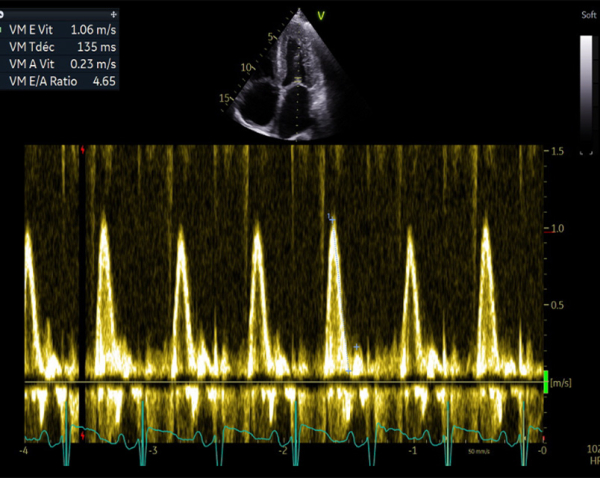

- Profil mitral restrictif, pressions de remplissage VG élevées (E/A =2.6, E/e’ moy = 22)

FEVG 40% en Simpson biplan, 45-50% visuellement. GLS -7%. Hypokinésie des bases et hyperkinésie de l'apex. VG non dilaté (DTDVG = 35mm, VTDVG =54ml/m2), hypertrophié (SIV = 18.5mm, PPVG = 19mm).